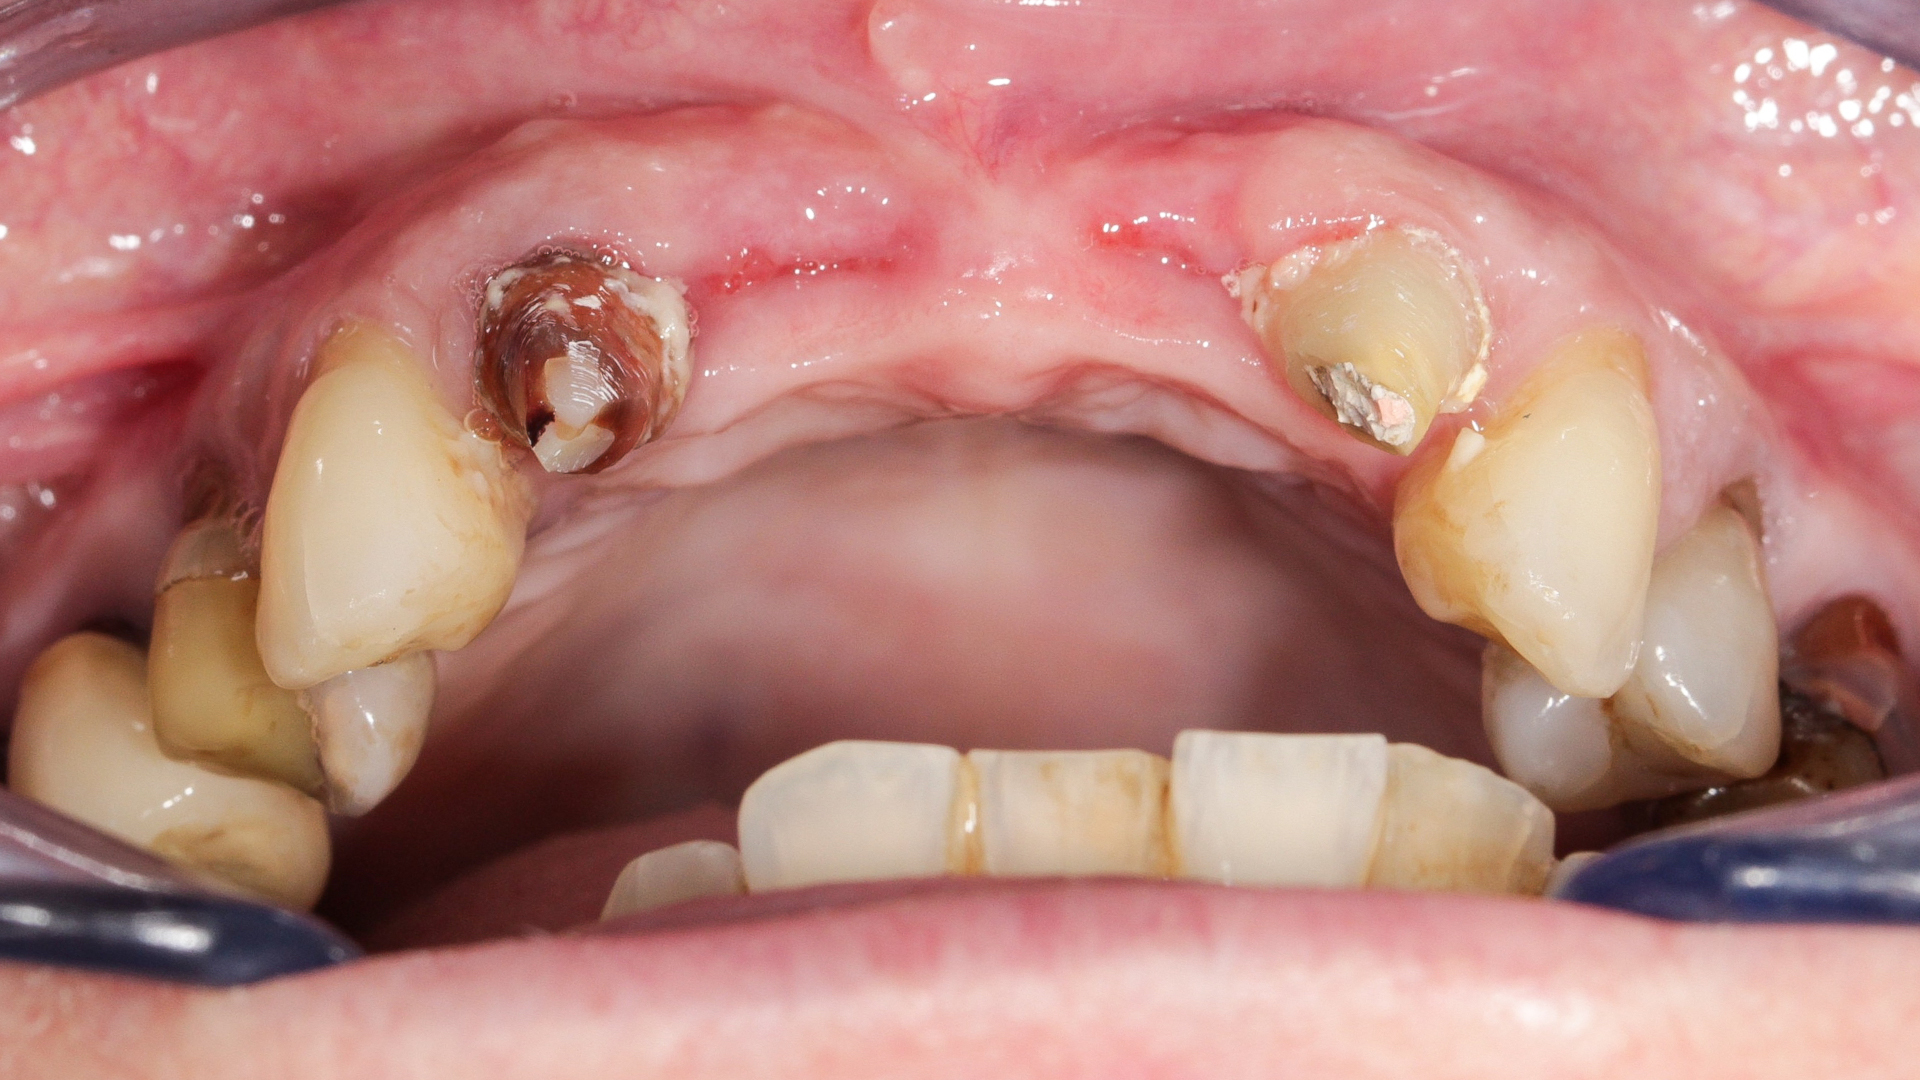

Une patiente de 49 ans nous a été adressée par l’un de nos confrères pour le remplacement de ses quatre incisives maxillaires (Fig. 23). Dans un contexte parodontal avancé, ses incisives centrales présentent une mobilité terminale (classe IV) elle n’ose plus les brosser de peur de les perdre lors de la manoeuvre. La patiente ne présente pas de problèmes de santé particuliers.

À l’examen, on observe une mobilité des quatre incisives maxillaires, une insuffisance osseuse verticale et horizontale, associées notamment au niveau de 11 et 21, la présence de plaque, de tartre et d’inflammation gingivale, surtout au niveau du bloc antérieur maxillaire. On note également la présence d’une dent de sagesse (dent 18) perdue (Figs. 24–26).